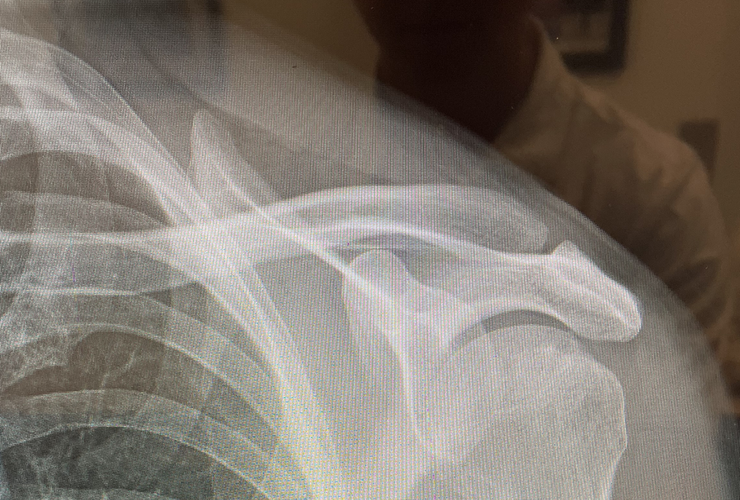

Image of a patient X-ray, used to decide when to use a REGENETEN Implant on a partial-thickness rotator cuff tear repair.

After reviewing his X-ray with his surgeon, Matt understood the extent of his injury and what was needed for the repair.